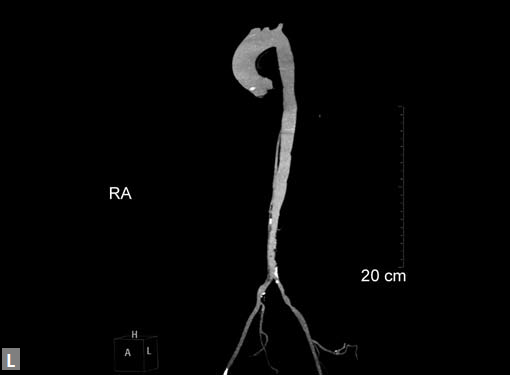

Connective tissue disease, hypertension and iatrogenic (Figs 19K to L) injury are the common causes for dissection. Radiologist not only establishes the diagnosis, also evaluates the extent of dissection, presence of thrombosis particularly in false lumen. In case of type A dissection, involvement of aortic root is determined. Relation of thrombosed lumen and ostia of coronary vessels, cephalad branches (Figs 19N, R to V) of aorta is determined. Most of the occasions membrane is demonstrated. Spiral nature of the membrane can be seen

Figs 19A to Y (A to C) Scannogram (A), plain (B) and contrast study (C) show partial anomalous pulmonary venous connection; (D to F) Heterotaxy; (G) Aortic occlusion; (H and I) Aortic stents; (J) Aortic dissection with ‘Benz’ sign due to second dissection within the true lumen; (K, L and M) Aortic dissection with thrombus in pseudolumen following catheter angiogram; (N) Aortic dissection involving common carotid arteries and subclavian artery; (O, P, Q and R) Aortic dissection with right renal artery arising from true lumen and left renal artery from false lumen; (S, T, U and V) Stanford B dissection with extension Y to iliac vessels; (W to Y) Aneurysmal dilation of ascending aorta